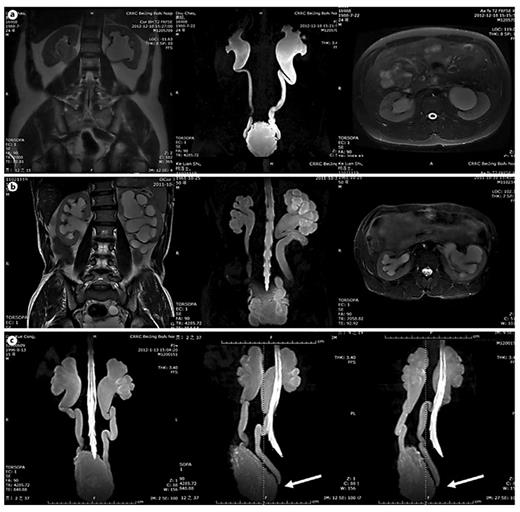

In table 1, LUTD is described according to the Guidelines of the European Association of Urology (EAU) [2] and the terminology of the International Continence Society (ICS) [5]. VUR was graded according to the IRSG, and kidney function was determined by the glomerular filtration rate from isotope renography and the serum level of creatinine. UUTD was graded as follows: grade 0, the central renal complex is closely apposed without UD (fig. 1a); grade 1, slight separation of the central renal complex exists, and the ureter is <7 mm in diameter (fig. 1b); grade 2, the renal pelvis is further dilated, a single or a few calices may be visualized and the ureter is <10 mm in diameter (fig. 1c); grade 3, the renal pelvis is dilated, there are fluid-filled calices throughout the kidney, the renal parenchyma overlying the calices has thinned (renal parenchyma loss <50%), and the ureter is tortuous and <15 mm in diameter (fig. 2a), and grade 4, similar to grade 3, but the renal parenchyma over the calices is thinned (renal parenchyma loss >50%), the ureter is severely tortuous and the ureter is >15 mm in diameter (fig. 2b). For NB patients, detrusor fibrosis and thickening secondary to progressive destruction of the bladder wall often result in ureteral strictures within the bladder wall and distal ureteral obstruction (fig. 2c), which is an important factor in the etiology of UUTD, including HN and UD, and often results in chronic renal failure. Therefore, this new system better discriminates among grade changes in UUT function, can provide objective indicators for UUT function and is an important component of long-term follow-up of conservative and surgical treatment (fig. 3).

Improvement of UUTD grades by MRU after 6 months of augmentation enterocystoplasty. a Preoperative UUTD grades of right and left kidneys were 3 and 4, respectively. b Postoperative UUTD grades of right and left kidneys became 0 and 1, respectively. A significant improvement is shown.